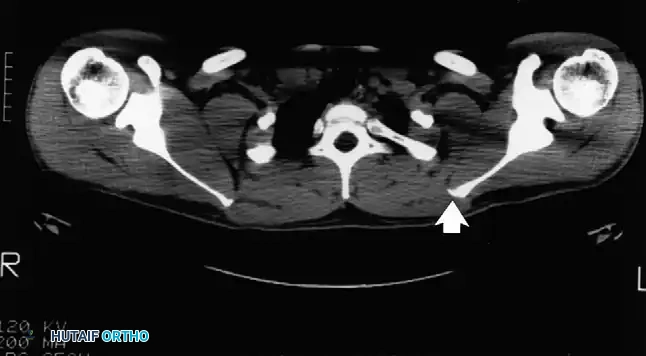

Snapping Scapula Syndrome (Scapulothoracic Crepitus)

Though not explicitly detailed in the raw extract, snapping scapula is a critical component of shoulder snapping syndromes. It is caused by the disruption of the smooth gliding motion between the anterior scapula and the posterior thoracic cage.

Pathologies include osteochondromas of the ventral scapula, Luschka's tubercle enlargement, or fibrotic bursitis (scapulothoracic bursitis). Advanced imaging, particularly CT scans with 3D reconstruction, is invaluable for identifying ventral scapular exostoses. Refractory cases are treated with arthroscopic or open partial scapulectomy (resection of the superomedial angle) and bursectomy, yielding high rates of symptomatic relief and restoration of normal shoulder kinematics.